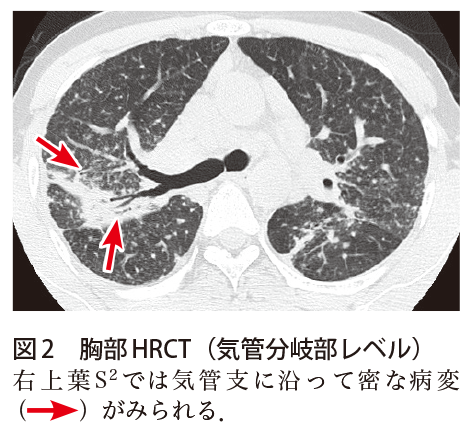

解答 解説 黄色痰 血痰を伴う咳嗽で受診した50歳代男性 実践 画像診断q A 羊土社 レジデントノート 羊土社